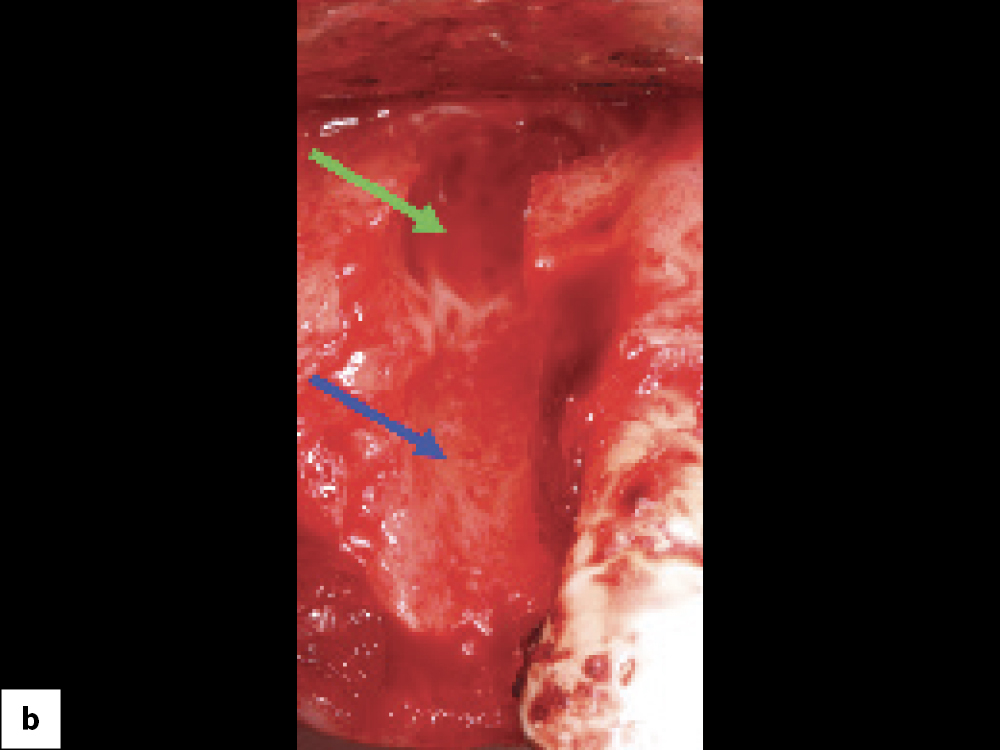

Bony Defect Evaluation A

Bony Defect Evaluation C

Bony defect evaluation: (a) Flap reflection allows the clinician to visually evaluate the size and location of the fenestration to determine whether the defect will compromise implant positioning or primary stability when immediate implant placement is desired; (b) Examples of a large fenestration (green arrow) and loss of the buccal plate (blue arrow), either of which would contraindicate immediate implant placement due to the inability to obtain primary stability; (c) Additional example of flap reflection to show the fenestration.